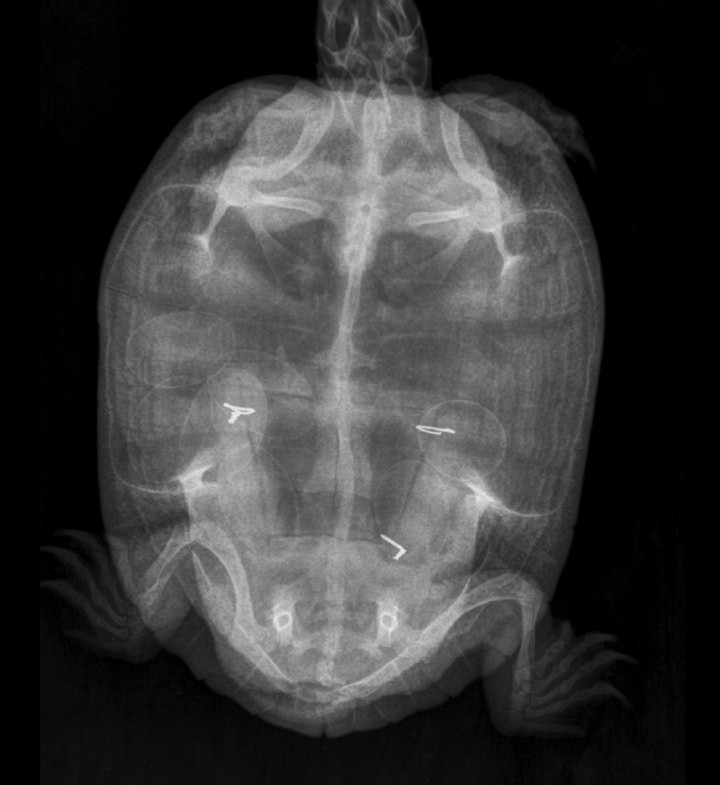

Dada la gravedad de la lesión se propone la realización de una celiotomía exploratoria. Para la planificación quirúrgica se obtiene una radiografía en la que no se detectan signos de obstrucción digestiva, distocia, ni otras anormalidades. Sobre la imagen radiológica se simula una ventana lo más caudal y amplia posible que permitirá la exploración de la cavidad celómica (Fig. 3). Asimismo, se realizan un microhematocrito y bioquímica sérica cuyos resultados no muestran anormalidades (Tabla 2[ Carpenter JW, Harms CA: En Carpenter´s exotic animal formulary (sixth edition), St Louis, Elsevier, 2023; 172-174. ]).

Simulación de la osteotomía sobre imagen radiológica.